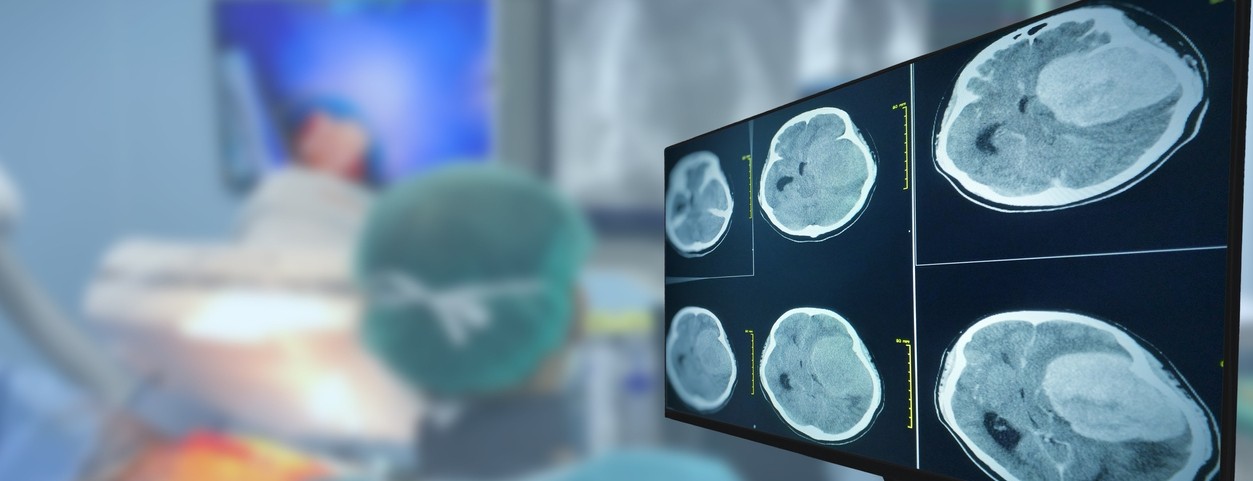

Featured photo at top of a CT brain scan. Photo/Tonpor Kasa/iStock.

New multi-institutional phase 3 clinical trial data published May 2 in Cell Reports Medicine found that a cancer stem cell test can accurately decide more effective treatments and lead to increased survival for patients with glioblastoma, a deadly brain tumor.